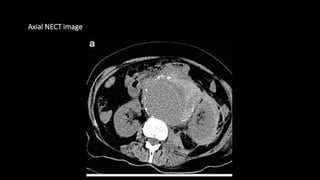

CT scan

• Most common finding is retro peritoneal

hematoma(density>50 HU)

•Extension of blood into pararenal spaces and psoas

muscle

• On CECT active extravasation of the contrast

Axial NECT image